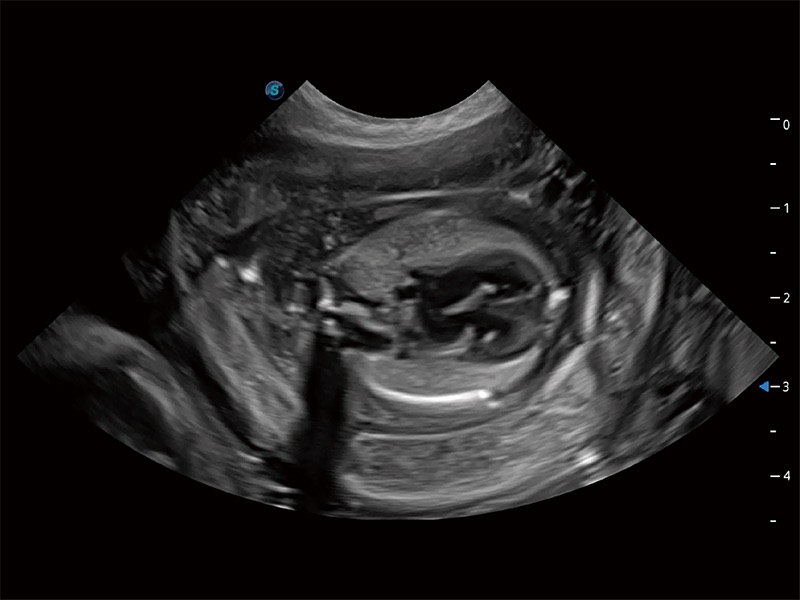

动物是人类最亲密的朋友和最值得信赖的伙伴。db真人体育官网也一直致力于探索动物专用的超声影像解决方案。全新推出的ProPet系列,是db真人体育官网在动物超声影像智能化、专业化、精准化的一次跨越式革新。动物不能用言语来表述自己的不适,通过超声影像,ProPet系列搭建了动物医生与不同物种沟通的“桥梁”,为动物医生注入了“治愈之力”。 ProPet 80 是db真人体育官网匠心打造的一款高端动物专用彩超,采用性能卓越的全新硬件架构,极大提升超声系统的运行效率和数据处理能力,帮助动物医生从容应对日益增多的挑战性病例和日益多样化的临床需求。

高性能和先进的临床应用工具可以为动物医生提供临床信心。ProPet 80 搭载了先进的腹部和浅表应用工具,帮助医生在日常临床实践中发挥前所未有的作用。

ProPet 80 全新的动物超声智能软件和丰富的探头群,为动物医生提供了高清晰度和精细分辨率的图像,无论在宠物、马科、畜牧还是实验室动物等应用中都可以轻松应对,为您的日常工作带来满意的体验。